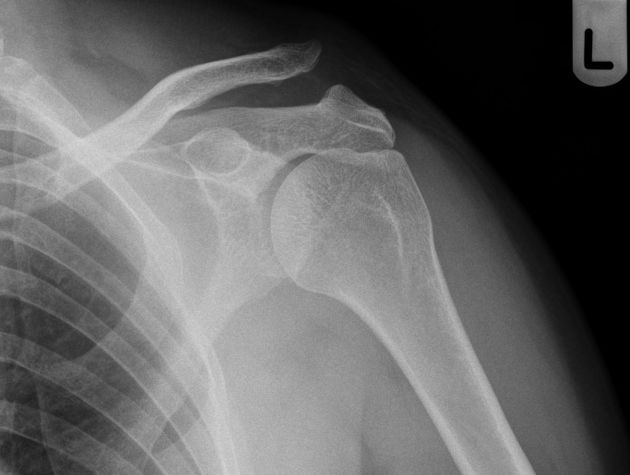

Example 2

Diagnosis

Acromioclavicular Joint Dislocation

Image 2: Gaillard, F., Knipe, H. Acromioclavicular joint injury. Reference article, Radiopaedia.org. https://doi.org/10.53347/rID-843